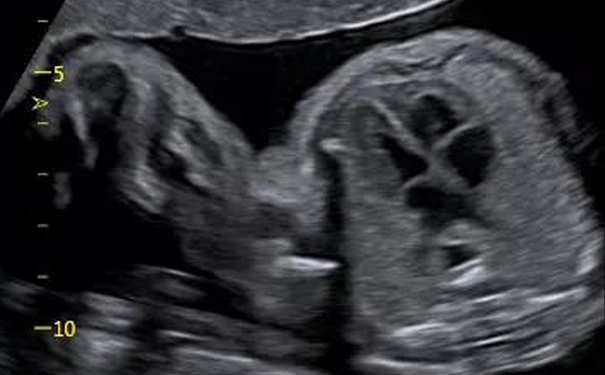

随着生命的持续孕育,心脏迅速成长,第八周时已基本成型。20周时,超声就能清晰地看心脏结构啦。

飞依诺彩超孕晚期胎心

孕中晚期胎心